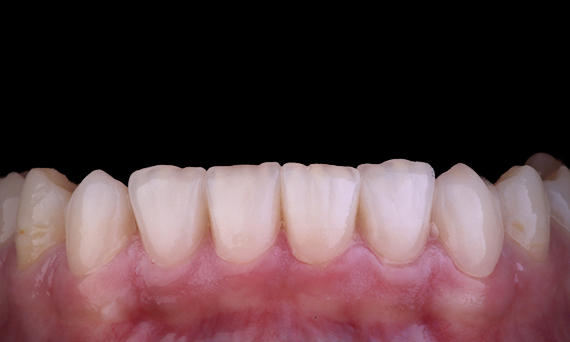

Before: The treatment objective was to rehabilitate the anterior maxilla and mandible for esthetic improvement. The clinical diagnosis revealed ameloenesis imperfecta.

After: Labside- fabricated restoration made from advanced lithium-disilicate ceramic CEREC Tessera and for the high esthetic result, the veneering with Celtra Ceram.